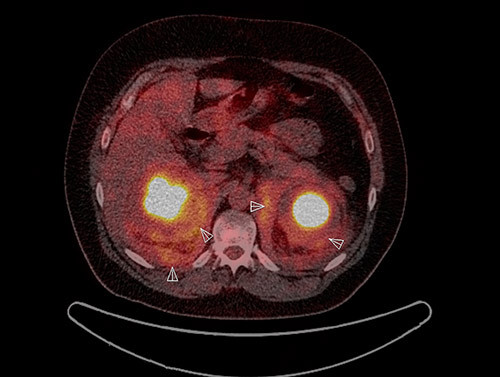

18FDG PET-CT viste økt opptak perirenalt, oppfyllinger i begge orbitae, periaortalt, i myokard og i oppfylling rundt hjertet samt i beinmargen i distale deler av begge femora og proksimale tibiae (fig 3, fig 4). I nyrene var det dilatasjon av calyces, men ikke dilatasjon av det ekstrarenale nyrebekken eller uretre. Ultralyddoppler av nyrearterier viste ikke tegn på nyrearteriestenose. I lungene var det lette mattglassfortetninger og sparsom bilateral pleuraeffusjon. Spirometri viste lett redusert belgfunksjon av restriktiv type. Ekkokardiografi viste grensestor venstre ventrikkel med god venstre og høyre ventrikkelfunksjon, i tillegg til lett perikardvæskebrem på 0,5 – 0,6 cm uten hemodynamisk betydning.

Pasientens multiorgansykdom affiserte vevet i øyehulene, aorta, perikard, perirenale områder og de lange rørknoklene. Erdheim-Chesters sykdom ble mistenkt, og det ble bedt om ny gransking av biopsiene fra orbita.

Ved ny gransking ble det poengtert at makrofagene hadde rikelig med lyst skummende cytoplasma, forenlig med skummakrofager. Immunfenotyping viste at de CD68-positive makrofagene var negative for CD1a og S100. Patolog konkluderte med at det morfologiske bildet passet med Erdheim-Chesters sykdom.

Den nye granskingen av biopsimaterialet sammenholdt med det kliniske bildet førte til at vi konkluderte med Erdheim-Chesters sykdom, en sjelden form for histiocytose med affeksjon av en rekke organer. Det ble derfor startet behandling med pegylert interferon-α.